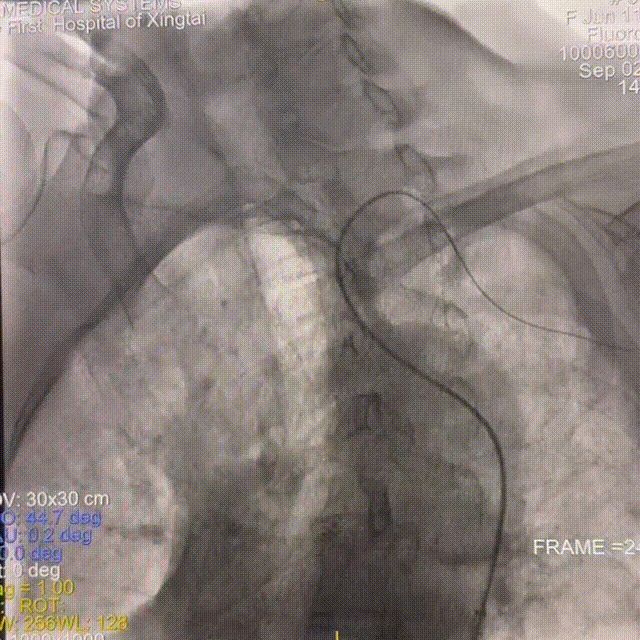

通路建立:右侧远桡动脉置鞘成功,5F多功能导管尝试超选右侧颈总动脉失败。

撤出多功能导管和短鞘,交换088输送导管至右侧锁骨下动脉近端,沿输送导管送入赛诺神畅APEX TRA GC™5F-130cm SIM2至主动脉弓,成袢后轻松超选入右侧颈总动脉,同轴沿SIM2导管将输送导管送入右侧颈总动脉,撤出SIM2导管,沿导丝将6F 115cm远端通路导管送至右侧颈内动脉C4段。

动脉长鞘怎么置入一技之“长”丨经桡及经股困难入路应用赛诺神畅APEX TRA GC™导引导管建立通路病例合集_https://www.jmylbn.com_新闻资讯_第33张

路图下上导丝、导管

动脉长鞘怎么置入一技之“长”丨经桡及经股困难入路应用赛诺神畅APEX TRA GC™导引导管建立通路病例合集_https://www.jmylbn.com_新闻资讯_第34张

SIM2导引导管超选右侧颈总动脉